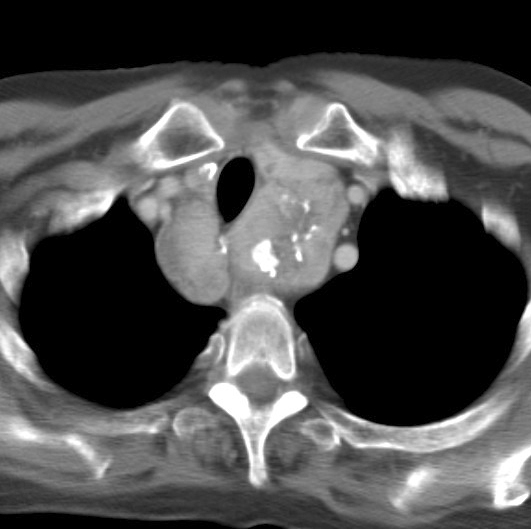

Thyroid Mass

Case 8 CT